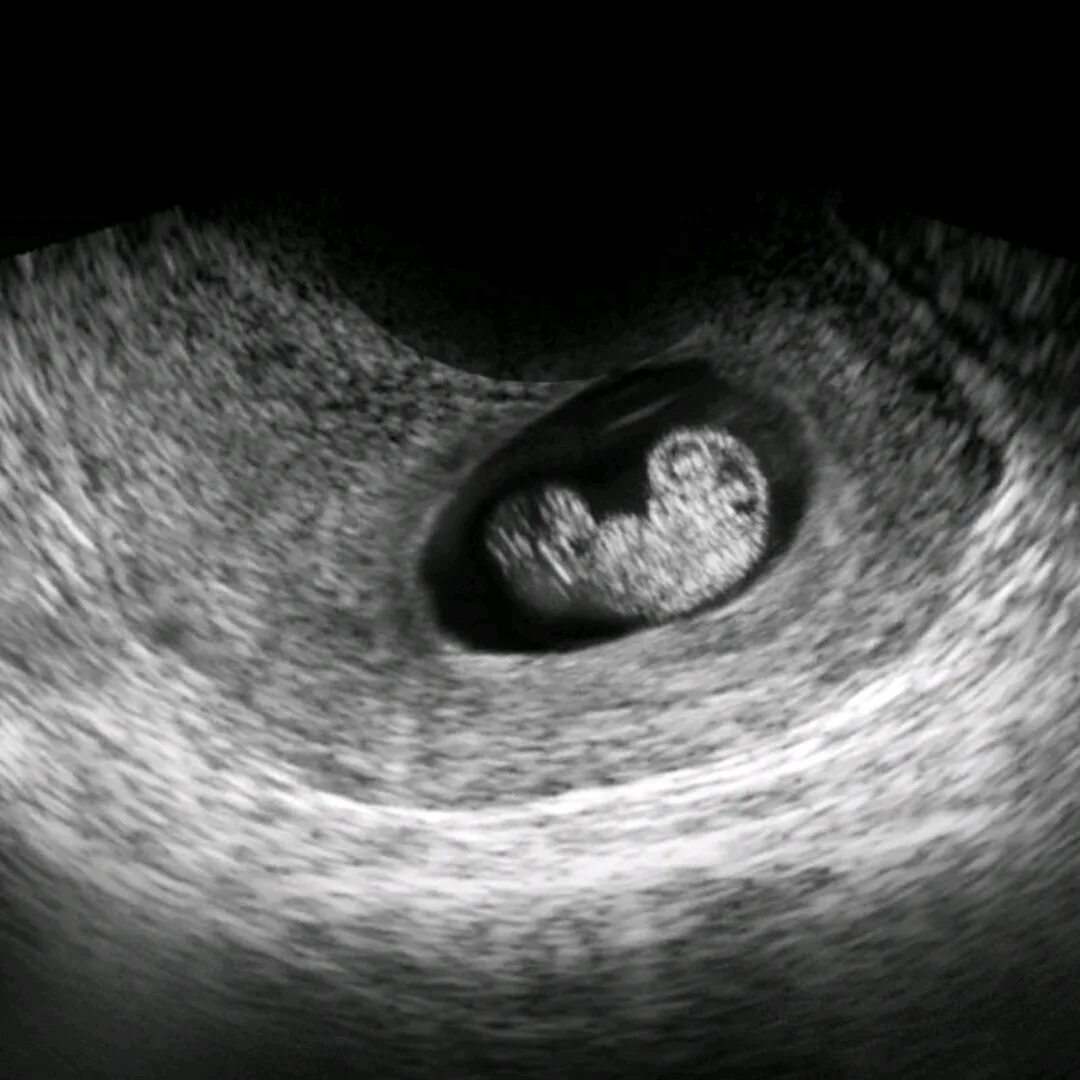

Эмбрион 7 дня форум